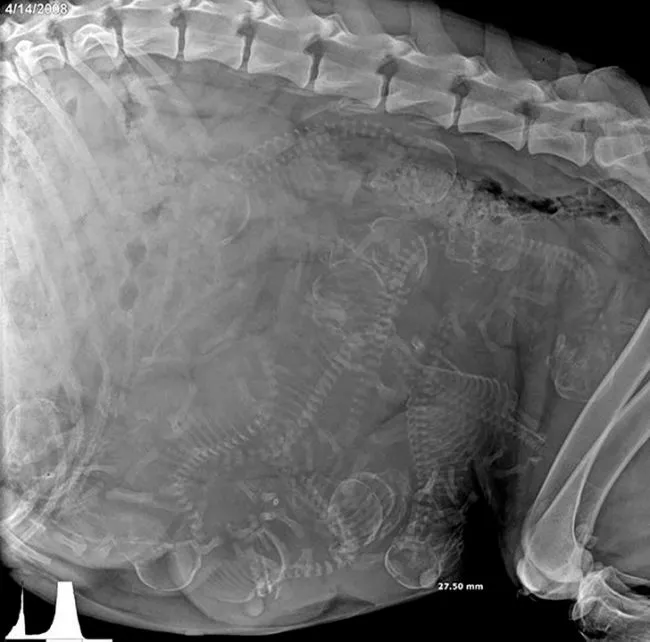

7 “ ภาพเอ็กซ์เรย์ของสุนัขตั้งท้อง”